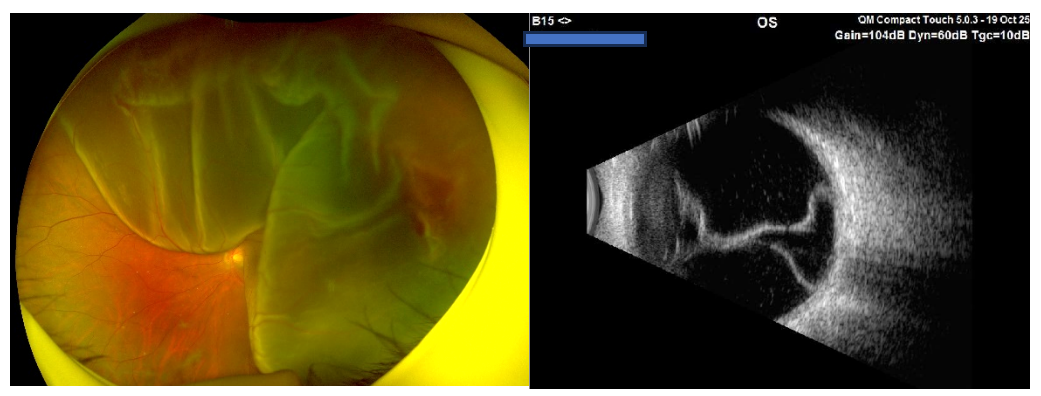

紧急的眼底检查,揭示了左眼残酷的真相:广泛的孔源性视网膜脱离,视网膜上可见多个裂孔。

检查证实,他的 视网膜已完全平伏复位,激光斑清晰可见。脱离的「底片」被成功抢救回来。